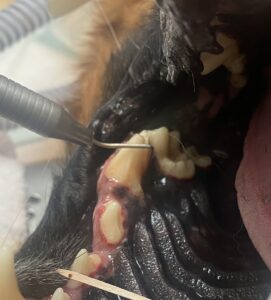

By Dr. Brook Niemiec

Let us share a little about Rypper, a VDS client and 9-year-old male German Shepherd.

Rypper is a classic example of why we must refrain from using the level of tartar to determine if a pet needs a dental procedure. He presented with mild tartar and gingivitis while being treated for a broken tooth. However, while under anesthesia, he was examined and radiographs taken, revealing severe periodontal disease to the distal (back) root.

Periodontitis represents a severe infection that was likely present for a long time and would’ve continued if Rypper had not been brought in for an unrelated matter. For these reasons, most veterinary dentists recommend annual cleanings regardless of outward evidence of disease. Especially in the case of Rypper, a German Shepherd and a breed not predisposed to gum disease, making this even more unexpected. Instead of treating periodontal disease, we advocate preventing it.

About Rypper’s tooth, extraction was a viable option, but because the front roots were healthy, we elected to section the tooth, extract the back root and perform a root canal on the front roots. This procedure saved half of the tooth and was far less invasive than extraction as the back root was easily removed.

Rypper recovered normally and, on recall the next day, was back to his normal self.